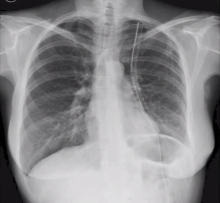

Patient: female, 46-years-old, non-smoker, no comorbidity

Diagnosis: 4 cm thymoma